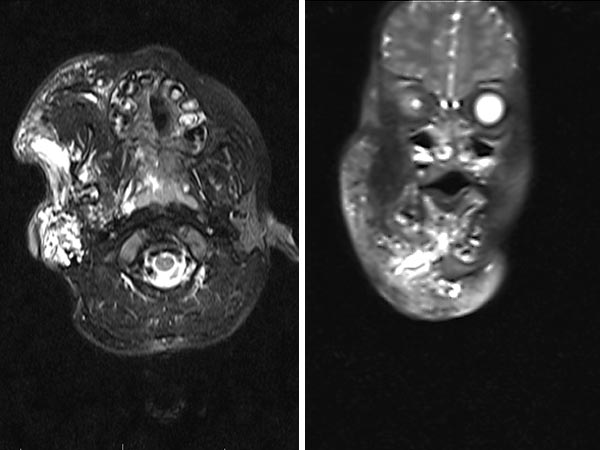

T2-weighted, fat-saturated MRI at 2 months of age shows the full extent of microcystic and macrocystic lymphatic malformation on axial image (left) and coronal image (right).